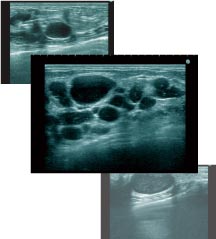

エコー検査

最先端のデジタル技術による乳腺用エコーで、触診だけでは見つけられない3つの状態を確認します。

ヒアルロン酸注入で豊胸施術を受けた後であっても、しこりの原因がそれに起因するとは限りません。別の問題であるケースも考えられますので、まずはしこりの原因を調べることが重要。そのために診断能力の高い医師が、大学病院でも使われている最新カラーエコーで検査します。

脂肪注入だと、皮下や乳腺下、大胸筋内など様々な層に分散させますが、ヒアルロン酸注入は異なります。皮下だと表面から近すぎて硬さが強調されてしまい、大胸筋内は吸収速度が早過ぎてバストアップ効果が得られません。そのため、通常であれば乳腺下と大胸筋下に分散して注入します。

しかし経験の浅いドクターの場合、皮下や乳腺組織内に注入してしまっていることもあります。そのようなケースにも対応するため、エコー検査でしこりの場所やサイズを確認することが重要です。